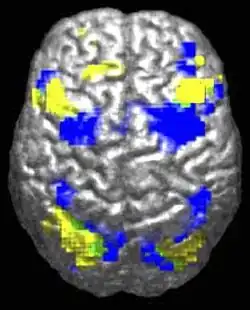

Функциона́льная магни́тно-резона́нсная томогра́фия, функциона́льная МРТ или фМРТ (англ. Functional magnetic resonance imaging) — разновидность магнитно-резонансной томографии, которая проводится с целью измерения гемодинамических реакций (изменений в токе крови), вызванных нейронной активностью головного или спинного мозга. Этот метод основывается на том, что мозговой кровоток и активность нейронов связаны между собой. Когда область мозга активна, приток крови к этой области также увеличивается[1].

ФМРТ позволяет определить активацию определенной области головного мозга во время нормального его функционирования под влиянием различных физических факторов (например, движение тела) и при различных патологических состояниях.